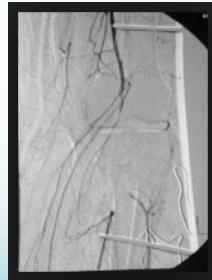

- Urgent reduction & vascular intervention if needed

- Then external fixation